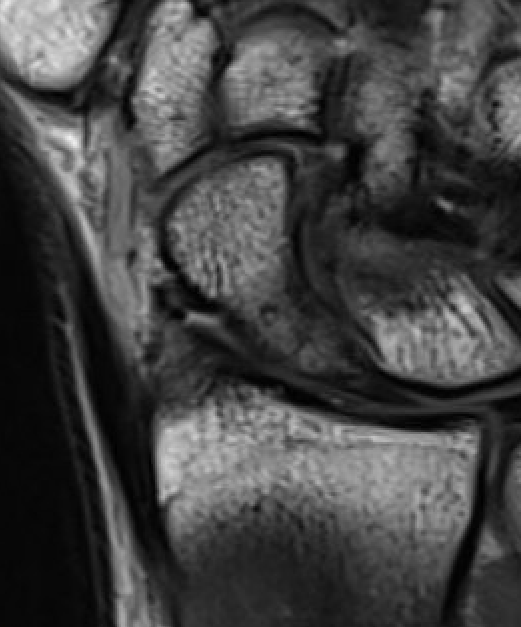

MRI

Indications

- occult fractures

- diagnosis of AVN

Occult scaphoid fracture on MRI

- 67 patients with normal xray and suspected scaphoid fracture

- 10% had scaphoid fracture on MRI

Dean et al Bone Joint Open 2021

- 258 patients with normal xray and suspected scaphoid fracture

- 13% had scaphoid fracture on MRI, 6% scaphoid contusion